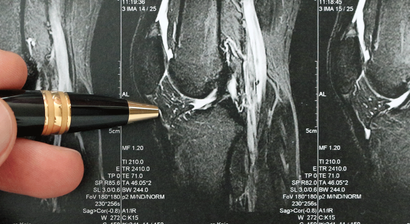

Knie- und Sportverletzungen Wien

"Was man oft macht, macht man gut“, daher habe ich mich bereits vor vielen Jahren auf bestimmte Leistungen spezialisiert, um meinen Patienten in jeder Hinsicht die bestmögliche Betreuung bieten zu können. In unserer Ordination bieten wir unseren Patienten eine hohe Expertise bei Knie- und Sportverletzungen an.

Wichtige Schwerpunkte meiner Arbeit sind u. a. die Abklärung und Behandlung von:

• Meniskusriss

• Kreuzbandriss

• Bandverletzungen des Kniegelenkes

• Patellaluxation (Kniescheibenverletzungen)

• Knorpelschäden und Arthrose sämtlicher Gelenke

• Sportverletzungen des Bewegungsapparates